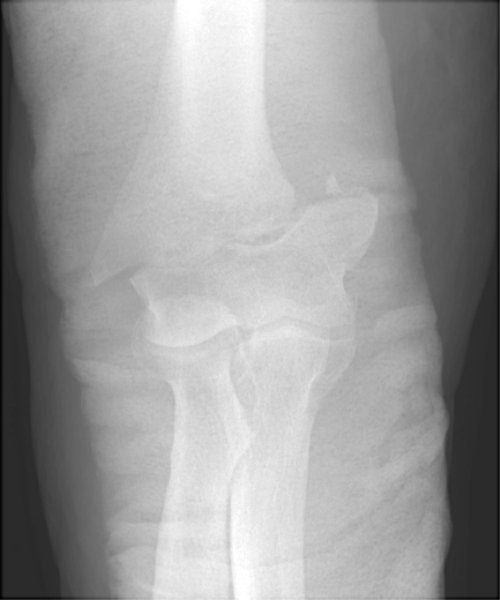

Return to Supracondylar Fracture (Humerus)